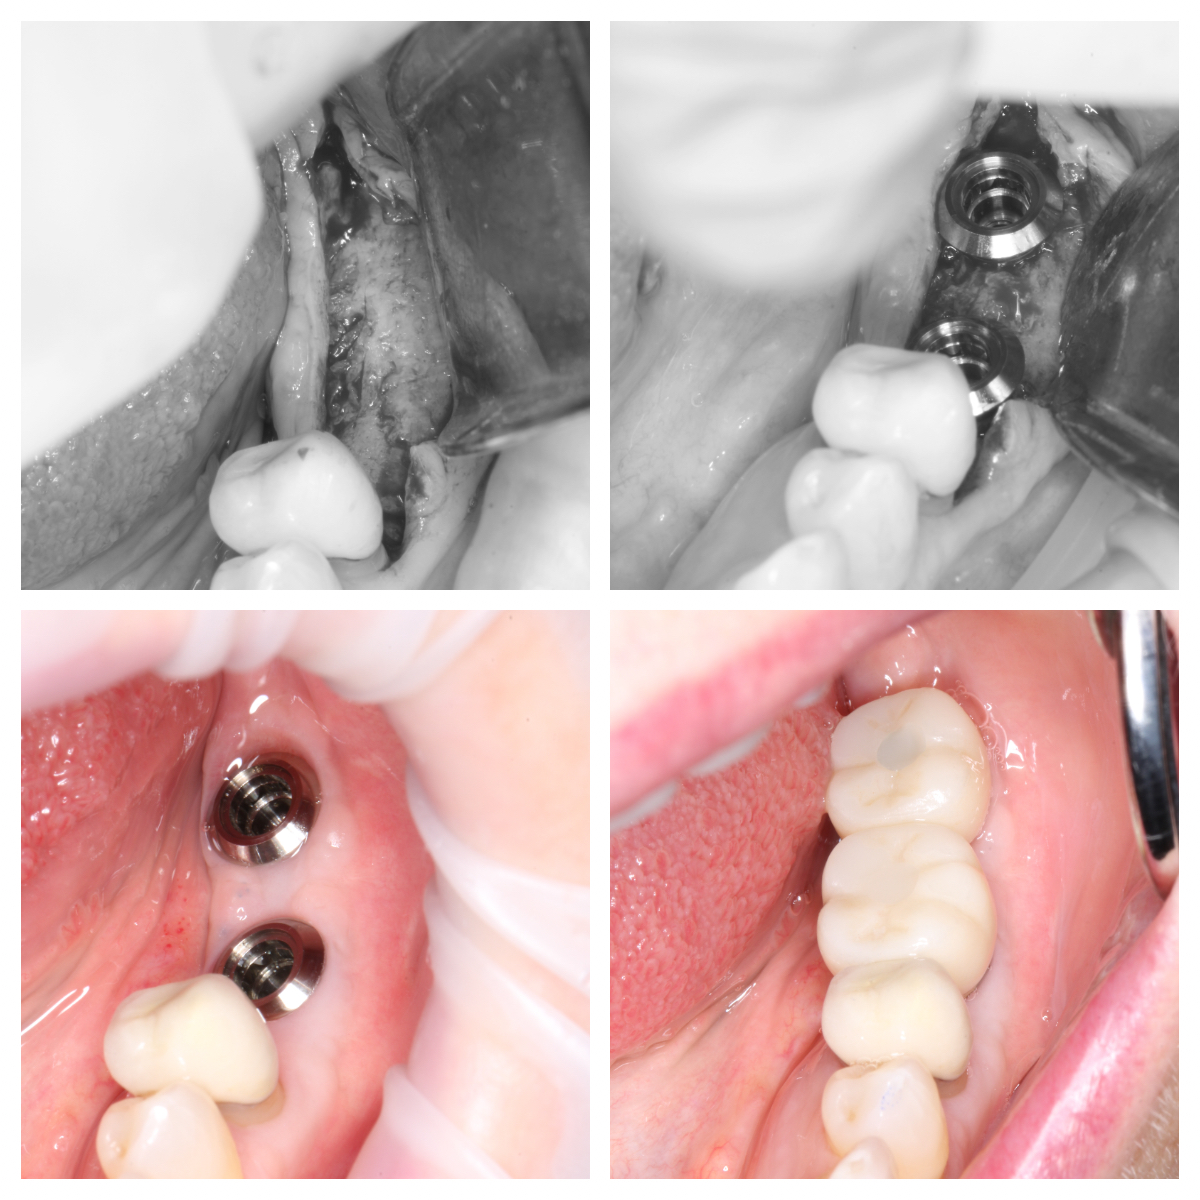

Immediate Implant Placement in Molar Extraction Site

immediate implant placement in molar site Dr. Noroozi